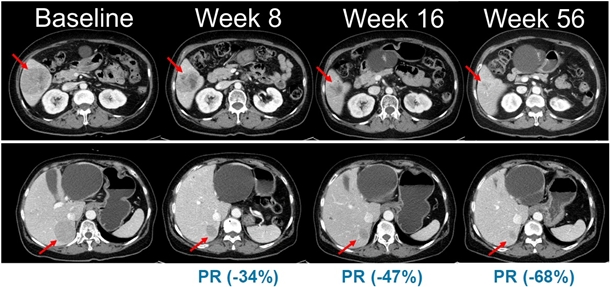

¡ã ½Ã°£ °æ°ú¿¡ µû¸¥ º´º¯ º¯È°¡ °üÂûµÈ º¹ºÎ CT ¿µ»ó